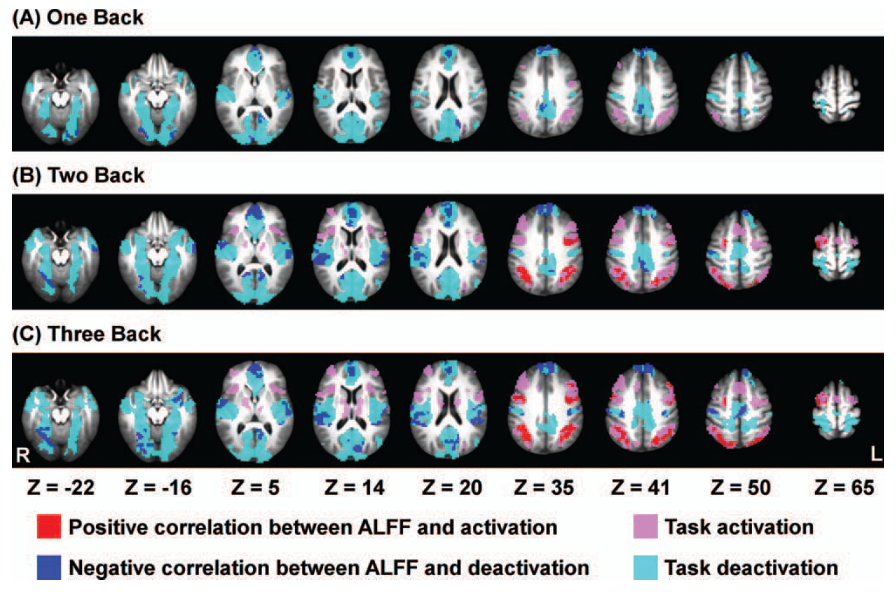

Results: CVR, RSF, and tasks

Motor task

Simon task, congruent responses

Simon task, incongruent responses

The relationship between CVR, RS fluctuations, and tIA

might be highly subject specific

or absent altogether.